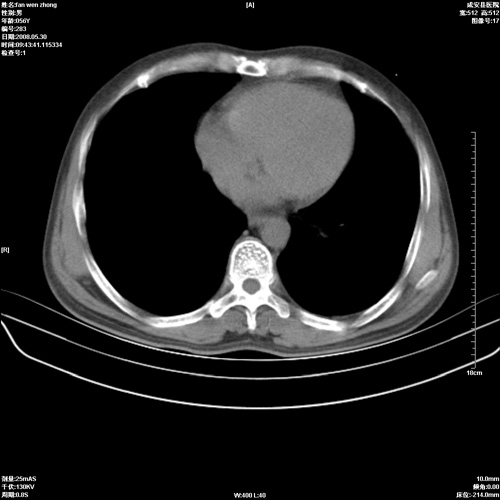

病人 男 56岁 一周前高热,体温达39-40度,经抗炎治疗后,体温渐降,达37,5-38度,轻微咳嗽,胸部不适 查白细胞为1.3万 行ct检查,请分析。

双肺内可见多发结节状病灶,并见小空洞,病人高热,白血球增高,应该是典型的迁徙性肺脓肿(多为金黄色葡萄球菌感染)。查一下口腔等其它部位有无感染灶。

双肺内可见多发结节状病灶,并见小空洞,病人高热,白血球增高,应该是典型的迁徙性肺脓肿(多为金黄色葡萄球菌感染)。建议治疗后复查.